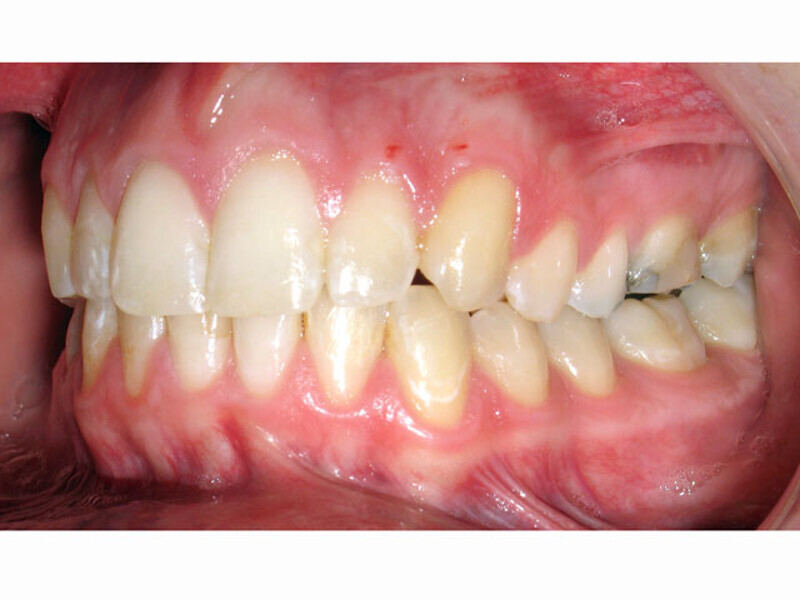

ClearCorrect treatment of crowding